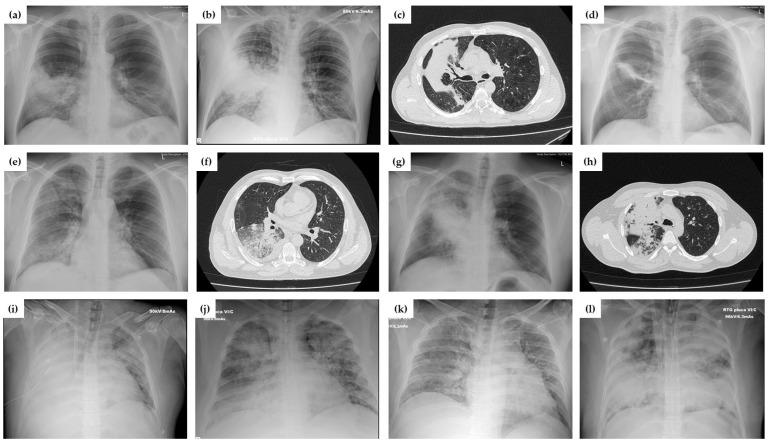

: While the concept of viral community-acquired pneumonia (CAP) changed with COVID-19, the role of non-influenza viruses as a cause of CAP is less clear. The aim of this study was to describe the clinical course, risk factors, inflammatory profiles, antibiotic use, outcomes and complications of adenoviral (AdV) CAP. : A prospective, non-interventional, observational cohort study included consecutively hospitalized immunocompetent adult patients with AdV CAP during an 18-month period. Clinical and laboratory data, including lymphocyte subpopulations and serum cytokine profiles were collected and correlated to clinical outcomes. : Fifty-eight patients with AdV CAP were included; 81% were males, with a median age of 33 (IQR 28-41) years and 62% without any comorbidities. All patients initially had high-grade fever for a median duration of 6 (5-7) days and respiratory symptoms. Increased CRP and procalcitonin, lymphopenia, mild thrombocytopenia and liver injury were frequent. Radiographic findings mimicked bacterial pneumonia (83% had unilateral involvement). Twenty-two patients (38%) had criteria for severe CAP, and these patients had higher procalcitonin, NLR, AST, ALT, LDH and CK, and lower T-lymphocyte CD4+ count. In comparison to influenza and bacterial CAP, patients with AdV had higher serum IL-2, IL-1β, IL-8, IL-10, CXCL10 and MCP-1, and lower TGF-β1 concentration. Thirteen patients required low-flow oxygen therapy, and 13 advanced respiratory support. Complications occurred in 29%, with one fatal outcome. While all patients received empirical antibiotic therapy, after AdV detection it was stopped in 21%, although only one patient had detected a possible bacterial coinfection. : Since AdV CAP in immunocompetent patients is clinically and radiologically indistinguishable from bacterial CAP, it is associated with prolonged clinical course and lack of clinical response to antibiotics. This emphasizes the importance of AdV testing which could lead to more rational antimicrobial treatment.

虽然随着新型冠状病毒肺炎(COVID-19)的出现,病毒性社区获得性肺炎(CAP)的概念发生了变化,但非流感病毒作为CAP病因的作用尚不清楚。本研究的目的是描述腺病毒(AdV)CAP的临床病程、危险因素、炎症特征、抗生素使用情况、结局及并发症。:一项前瞻性、非干预性观察队列研究纳入了18个月期间连续住院的免疫功能正常的成年AdV CAP患者。收集临床和实验室数据,包括淋巴细胞亚群和血清细胞因子谱,并与临床结局相关联。:纳入了58例AdV CAP患者;81%为男性,中位年龄33(四分位间距28 - 41)岁,62%无任何合并症。所有患者最初均有高热,中位持续时间为6(5 - 7)天,并伴有呼吸道症状。CRP和降钙素原升高、淋巴细胞减少、轻度血小板减少和肝损伤较为常见。影像学表现类似细菌性肺炎(83%为单侧受累)。22例(38%)患者符合重症CAP标准,这些患者的降钙素原、中性粒细胞与淋巴细胞比值、谷草转氨酶、谷丙转氨酶、乳酸脱氢酶和肌酸激酶水平较高,T淋巴细胞CD4 +计数较低。与流感和细菌性CAP相比,AdV患者的血清白细胞介素-2、白细胞介素-1β、白细胞介素-8、白细胞介素-10、CXC趋化因子配体10和单核细胞趋化蛋白-1水平较高,转化生长因子-β1浓度较低。13例患者需要低流量氧疗,13例需要高级呼吸支持。29%的患者出现并发症,1例死亡。虽然所有患者均接受了经验性抗生素治疗,但在检测到AdV后,21%的患者停用了抗生素,尽管只有1例患者检测到可能的细菌合并感染。:由于免疫功能正常患者的AdV CAP在临床和影像学上与细菌性CAP难以区分,它与临床病程延长及对抗生素缺乏临床反应有关。这强调了AdV检测的重要性,其可导致更合理的抗菌治疗。